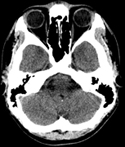

A CT scan is a diagnostic test that takes cross sectional pictures of the patient's internal anatomy. A CT scan creates highly detailed, cross sectional images of body parts and internal organs. CT can show bone and soft tissue structures such as internal organs, muscles, and blood vessels. It can be utilized to detect and diagnose a wide variety of medical conditions and abnormalities of nearly any body organ. A CT scan may require a contrast media such as barium or IV contrast to better highlight abnormalities. These examinations are performed by certified technologists, and every examination is directly supervised and interpreted by board certified radiologists.

A CT scan is made up of a series of x-rays which are processed by a computer to produce cross-sectional pictures of the body. These cross-sectional images allow one to look at the inside of the body.

- Head